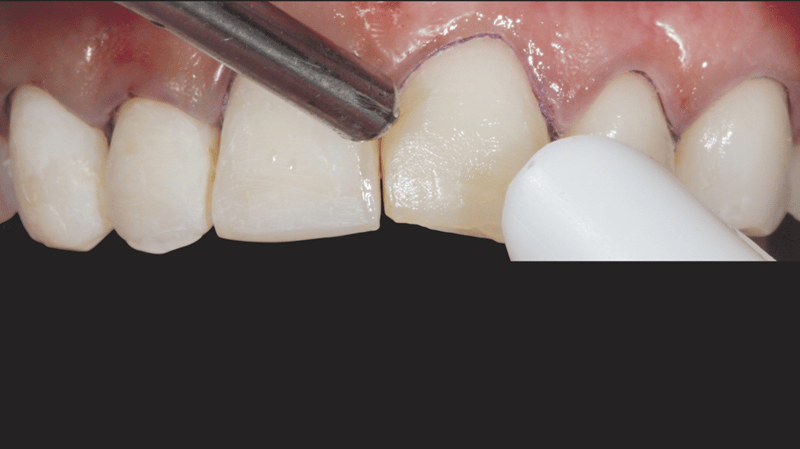

- Veneer-Separation: Vorsichtige und präzise Separation der Veneers mit Hilfe eines Skalpells (Nr. 12) und einem Separierstreifen.

- Gingivale Sulkuspräparation: Legen eines gestrickten Ultrapak™ Retraktionsfadens (Größe 0) in den gingivalen Sulkus, zwecks Vorbereitung des Ätzvorgangs.